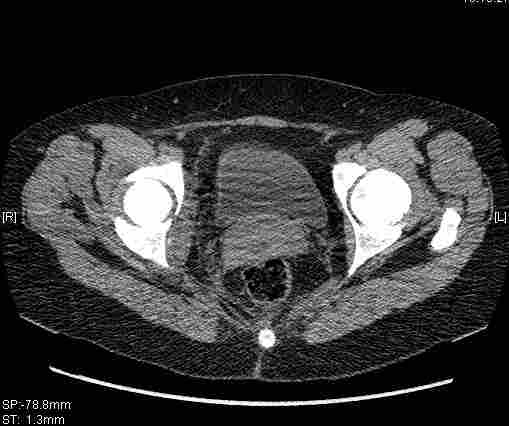

Re: Т-образный перелом вертлужной впадины

Удалось сегодня вывести пациентку в соседнюю больницу, где есть кт. Срезы сделаны только горизонтальные.